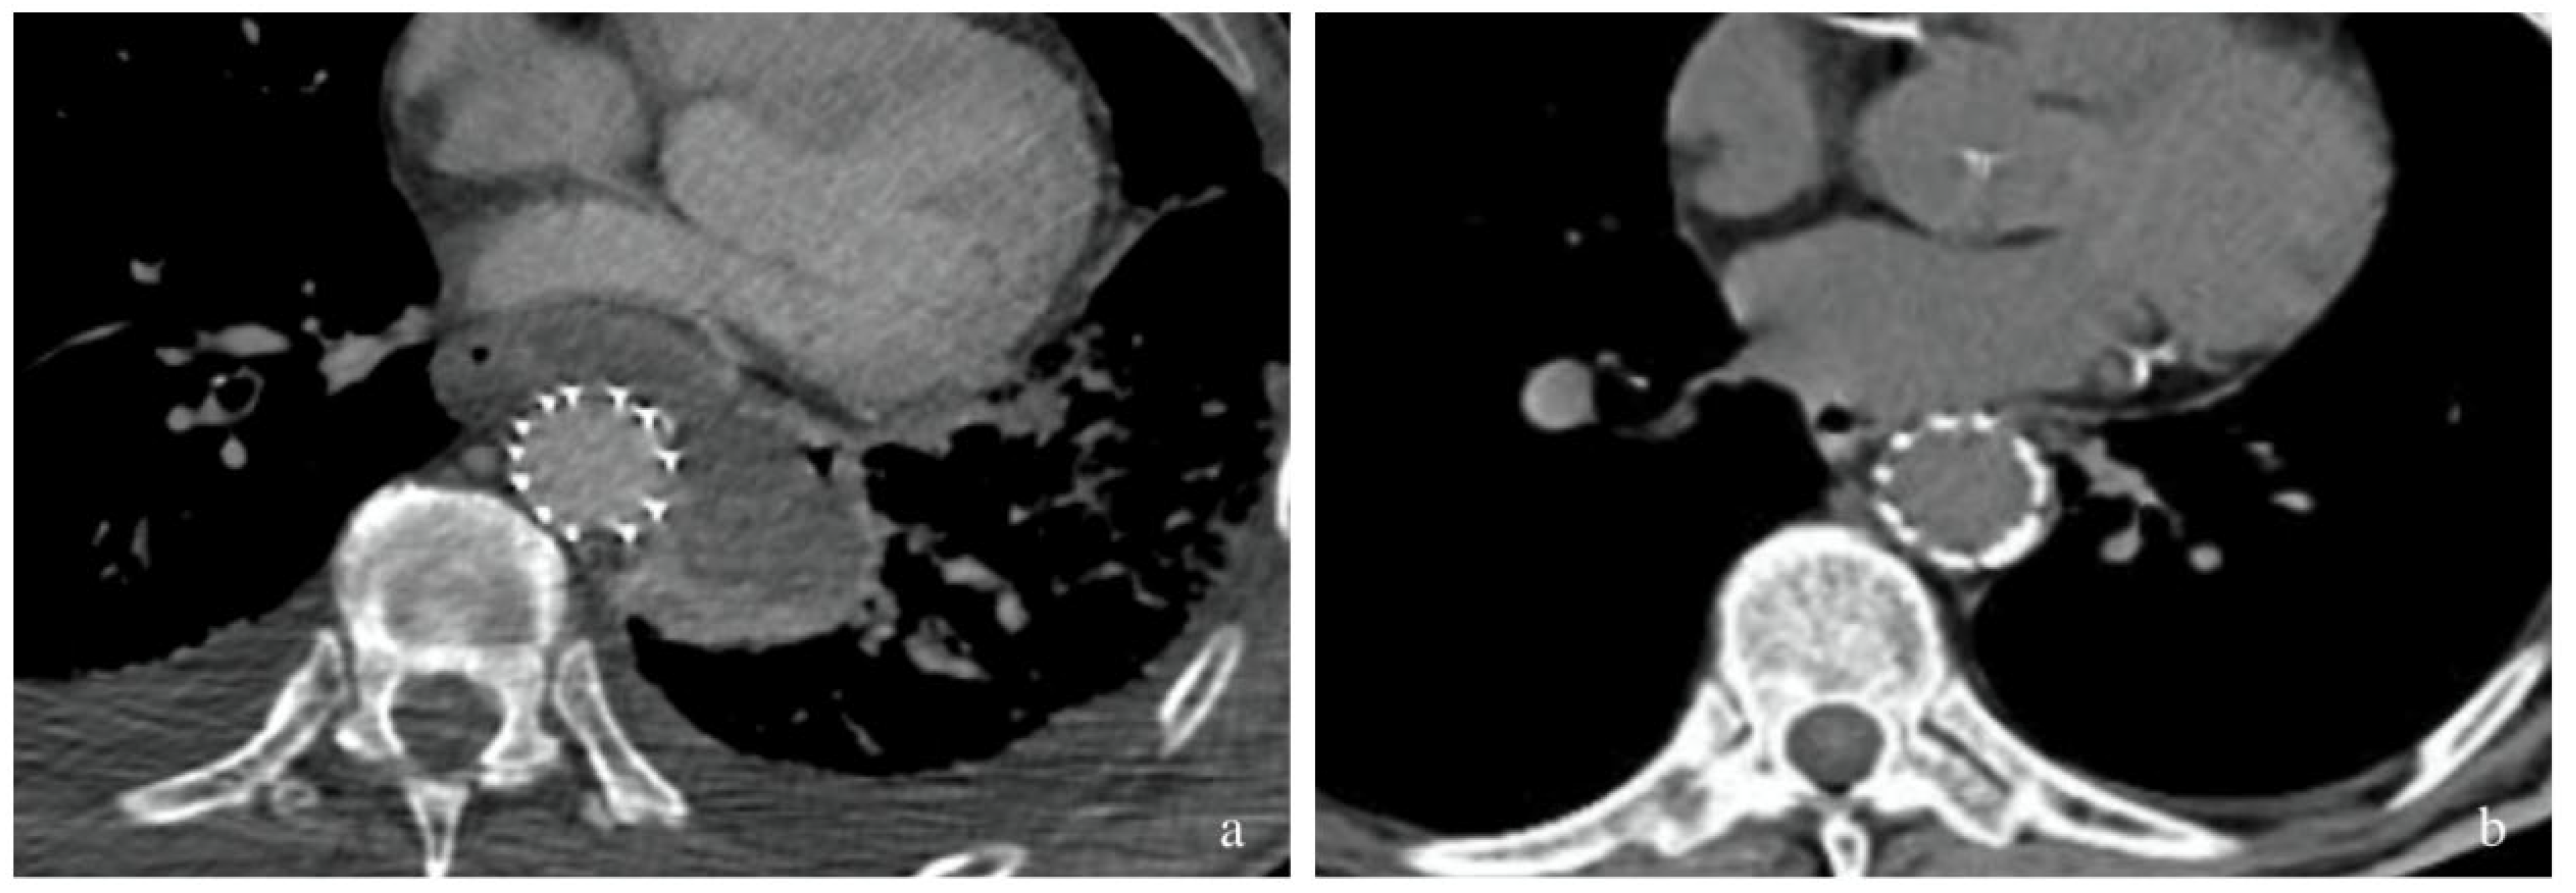

2.1. Case 1

2.2. Case 2